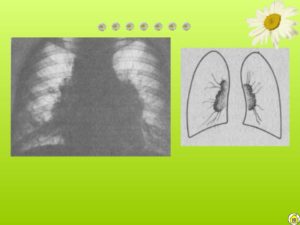

При застойных легких увеличение корней обусловлено расширением легочных вен, лучеобразно сходящихся от периферии к корням. Поэтому отграничение области корней от легочной ткани не резкое, что почти всегда позволяет дифференциацию от опухоли. Густота тени постепенно веерообразно убывает по направлению к периферии.

Обе стороны обычно поражены равномерно В случаях застоя в области корней легких, рентгенологически выраженных, почти всегда имеются также и аускультативные признаки застоя в легких: средне-крупнопузырчатые хрипы в обоих легких, особенно в нижних отделах, преимущественно справа; правосторонний плевральный выпот может еще не быть выраженным.

Наличие других явлений, указывающих на заболевание сердца, — увеличение сердца или изменение конфигурации его, аускультативные признаки порока сердца или ритм галопа и другие симптомы гемодинамической сердечной недостаточности — облегчают дифференциальный диагноз. Естественно, что застойные явления в легких находят прежде всего при недостаточности левого желудочка или при наличии затруднений перед этой частью сердца, т. е. при гипертонической болезни, аортальной недостаточности и митральных пороках.